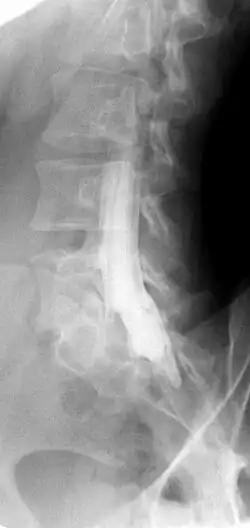

Die Myelographie bzw. Myelografie ist ein bildgebendes Verfahren, bei dem ein Kontrastmittel in den das Rückenmark (griechisch Myelon) enthaltenden Wirbelkanal (genannt auch Rückenmarkskanal) gespritzt wird und anschließend eine Röntgenaufnahme durchgeführt wird.

Vor der Entwicklung der als „Großradiologie“ bezeichneten Computertomographie (CT) und Kernspintomographie (MRT) war es schwierig, Bandscheibenvorfälle und andere Raumforderungen im Wirbelkanal zu beurteilen. Die Myelografie bietet eine Möglichkeit der weiterführenden Diagnostik. Zwischen den Wirbelbögen des dritten und vierten Lendenwirbels wird eine Spezialkanüle eingeführt (Lumbalpunktion), die bis in den Duralsack (Liquorraum) reicht. Die Lage ist dann korrekt, wenn Rückenmarksflüssigkeit aus der Kanüle tropft. Walter Dandy berichtete 1925 über erste Erfahrungen mit der Luftmyelographie.[1] In Deutschland wurde die Myelographie insbesondere nach den umfassenden Forschungsarbeiten von Herbert Peiper eingeführt, der dieses Forschungsthema in seiner Habilitationsarbeit Die Myelographie im Dienste der Diagnostik von Erkrankungen des Rückenmarks 1926 bearbeitete.[2]

Bei Verfügbarkeit der nichtinvasiven modernen Schnittbildverfahren MRT und CT hat die Bedeutung der Myelografie in der Humanmedizin abgenommen. Jedoch hat die Myelografie bei speziellen Fragestellungen in der Neurochirurgie und bei Nichtdurchführbarkeit von CT oder MRT immer noch ihre Indikation. Prinzipiell diente die Myelografie vor allem der Diagnostik von Raumforderungen im Spinalkanal. Bei der Auswertung ist auf Kontrastmittelabbrüche und -aussparungen zu achten. In der Tiermedizin spielt die Myelografie aufgrund der geringeren Verfügbarkeit von MRT und CT immer noch eine große Rolle.

Bei spinalen Wurzelkompressionssyndromen kann in einer Myelographie der Vorteil der dynamischen Aufnahmemöglichkeit genutzt werden, um Füllungsdefekte der sogenannten Wurzeltaschen nachzuweisen. Daher dient die Myelografie präoperativ zur Klärung offener Fragen, wenn ein MRT oder CT nicht oder nicht artefaktfrei (z. B. bei Skoliose) durchgeführt werden können.